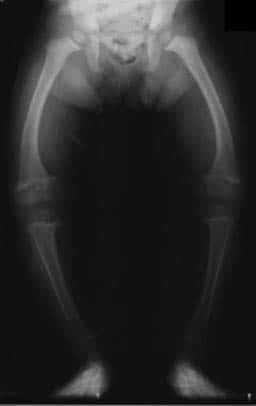

Fig 1.3 - Radiograph of a child affected with rickets.

Fig 4

Radiograph of a child affected with rickets.

Rickets is Vitamin D or calcium deficiency in children with growing bones. This means that the osteoid mineralises poorly and remains pliable. The epiphyseal growth plates can then become distorted under the weight of the body, potentially leading to skeletal deformities.